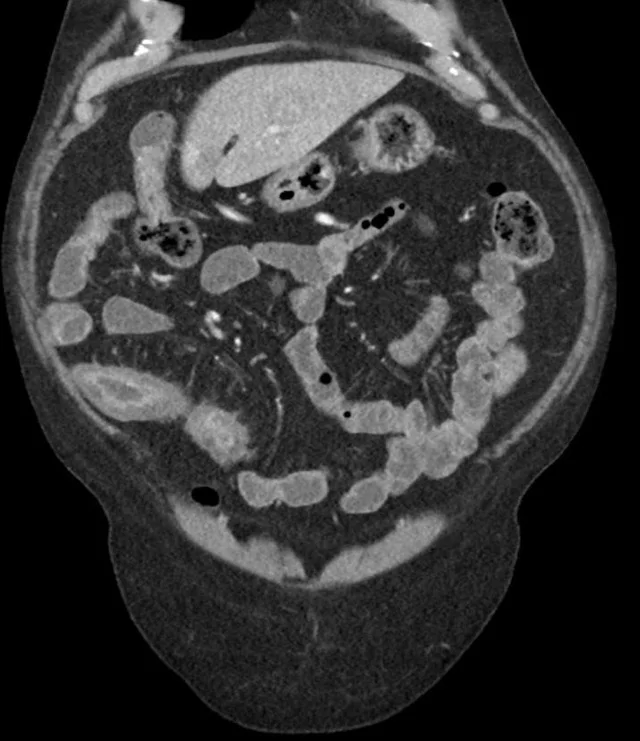

哎呀,说到克罗恩病,真是让人头疼不已!这病啊,就像个顽皮的孩子,时不时地就来捣乱一下,让人不得安宁。你知道吗,克罗恩病是一种慢性炎症性肠病,它会攻击我们的肠道,让肠道变得红肿、疼痛,甚至还会出现溃疡。这可不是什么小打小闹的病,它可是会影响到我们的饮食、生活,甚至心理健康的。

得了克罗恩病,生活简直就是一场没有硝烟的战争。每次吃饭都得小心翼翼,生怕一不小心就引发了症状。肚子疼、腹泻、体重下降,这些都成了家常便饭。有时候,真的觉得好无助,好想大喊一声:“为什么是我?”

但是,别灰心!虽然克罗恩病目前还没有根治的方法,但医学界可是在不断进步的。通过药物治疗、饮食调整、甚至是手术,我们可以有效地控制病情,减轻症状。虽然这条路可能很漫长,很艰难,但只要我们不放弃,总有一天,我们可以和这个顽皮的“孩子”和平共处。